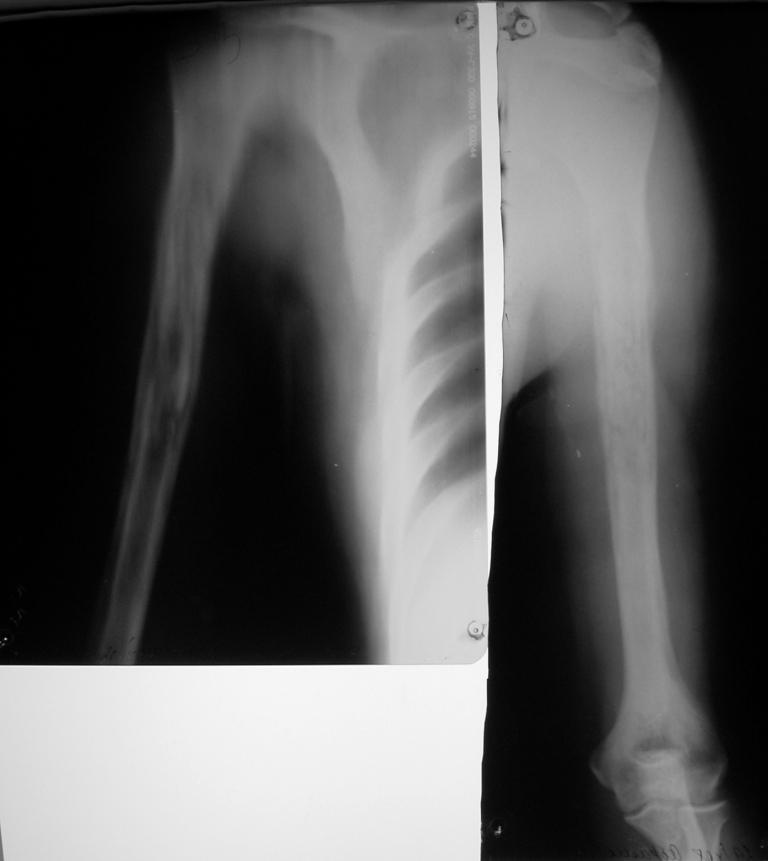

Остеомиелит плеча

К гнойным хирургам обратился больной 1982 г. р.

- После ушиба мягких тканей в сентябре сего года и применения тепловых процедур через 3 недели открылся свищ. Подскажите что делать? Может быть римирование костномозгового канала ppcntv цемент с антибиотиком?